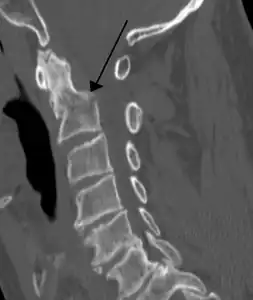

Fracture of dens

Fractures of the dens, not to be confused with Hangman's fractures, are classified into three categories according to the Anderson Alonso system:

• Type I fracture - Extends through the tip of the dens. This type is usually stable.

• Type II fracture - Extends through the base of the dens. It is the most commonly encountered fracture for this region of the axis. This type is unstable and has a high rate of non-union.

• Type III fracture - Extends through the vertebral body of the axis. This type can be stable or unstable and may require surgery.